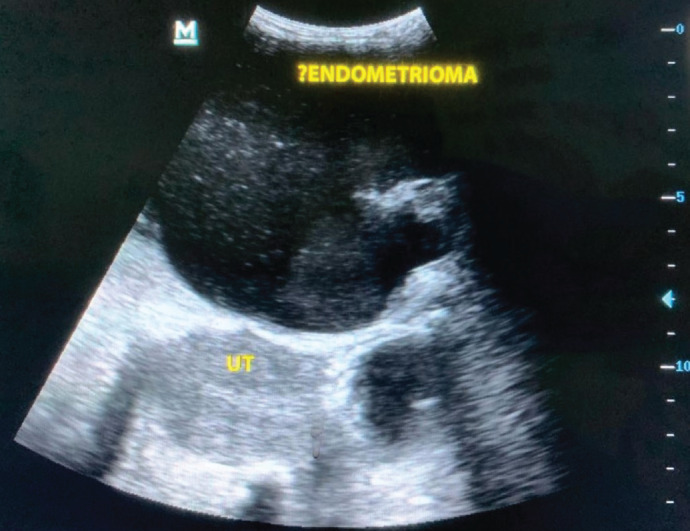

What is your diagnosis?